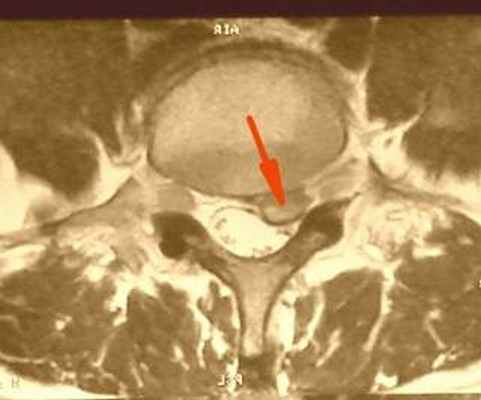

![]() | Фораминальная грыжа диска - редкий тип грыж диска, может сочетаться с истмическим спондилолизом, который в свою очередь дагностируется при спиральной компьютерной томографии. Сложен в диагностике, так как в просвете позвоночного канала грыжи не находят, но боли очень сильные. В этом случае небольшая - 3-4мм грыжа диска располагается в самом узком месте - фораминальном отверстии, где совсем небольшой кусочек хряща может сильно зажать нервный корешок. Лечение исключительно хирургическое. |

Под фораминальной грыжей позвоночника понимают выпячивание фиброзного кольца межпозвоночного диска за пределы его нормального анатомического расположения в фораминальное отверстие - место, где располагаются корешки спинномозговых нервов.

Этот вид грыжи считается наиболее опасным, так как в результате выхода фиброзного кольца происходит защемление нервных корешков. При этом пациент испытывает сильные болевые ощущения, нарушается двигательная активность, что значительно ухудшает качество жизни больного.

Чтобы понять что такое грыжа и как она образуется следует сначала рассмотреть как выглядит здоровый сегмент позвоночника с межпозвоночным диском. Межпозвоночный диск состоит из фиброзного кольца и пульпозного ядра желеобразной консистенции. В непосредственной близости с диском проходит спиной мозг в твердой мозговой оболочке. Отходящий от него спино-мозговой нерв с чувствительным и двигательным корешком лежит в костном ложе – фораминальном отверстии. В нормальных условиях в нем достаточно места для данного нервного образования. Фораминальная грыжа диска l4 l5 – это выпячивание фиброзного содержимого хряща за его нормальные пределы в фораминальное пространство. В результате такого выпячивания происходит ущемление спинномозгового нерва, что, безусловно, вызывает сильные болевые ощущения и становится причиной нарушения двигательной активности и работоспособности человека. Именно этот вид грыжи считается наиболее опасным.